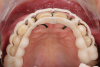

Fig 19. Verification of preparations with 3D-printed quality control guides in situ: front view (Fig 19), right lateral view (Fig 20), occlusal view (Fig 21).

Figure 19

Fig 20. Verification of preparations with 3D-printed quality control guides in situ: front view (Fig 19), right lateral view (Fig 20), occlusal view (Fig 21).

Figure 20

Fig 21. Verification of preparations with 3D-printed quality control guides in situ: front view (Fig 19), right lateral view (Fig 20), occlusal view (Fig 21).

Figure 21